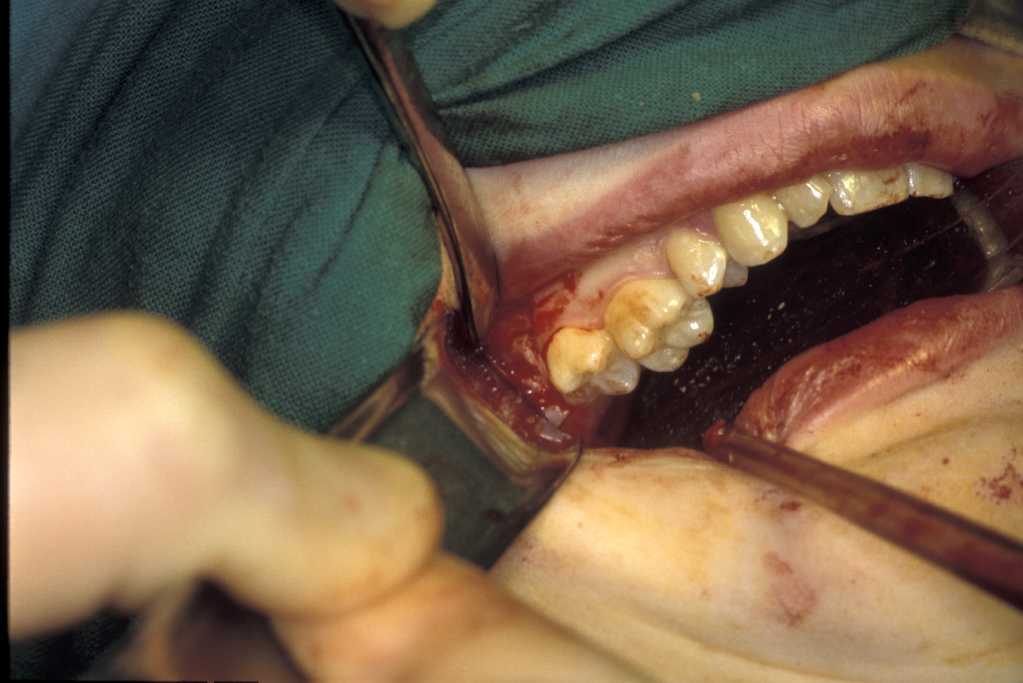

Surgical technique for removal of upper third molars involves a buccal flap. The flap is raised with an incision either around the second molar or a ‘slash’ passing from the distobuccal cusp into the buccal sulcus (Figure 13). Bone can often be removed buccally with a Coupland’s elevator (Figure 1) and the tooth then elevated with a Warwick-James or Cryer’s elevator. Deeply placed teeth rarely cause symptoms and are probably best left alone. Beware the fused, ankylosed or multirooted upper third molar (Figure 14).